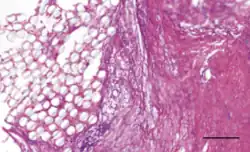

The Ligament Advanced Reinforcement (LARS) is a leading artificial ligament in ACL repair surgery. They are made of polyethylene terephthalate (PET).[3] They consist of an intraosseous and an intra-articular portion. The intraosseous section consists of longitudinal fibers bounded by a knitted transverse structure. This knitted structure can help prevent deformation and abrasion.[5][11] The intra-articular portion is made of longitudinal fibers pretwisted at a 90 degree angle. This section is designed to resist fatigue and promote tissue ingrowth.[5] Leeds Keio ligaments consist of a polyester mesh structure. It seeks to mimic the mechanical properties of the native ACL. The porous nature of the ligament can promote tissue ingrowth which has been shown to improve mechanical properties.[5] The PGA Dacron artificial graft consists of 75% braided biodegradable polyglycolic acid and 25% permanent Dacron thread.[11] The Kennedy LAD artificial ligament is made of polypropylene ribbons. It is designed to promote tissue ingrowth and the progressive transfer of load onto the new ligament.[10]

The native ACL of a human has a tensile strength on the order of kilonewtons,[3] and an elongation at failure of approximately 10%.[10] The mechanical properties of the native ACL vary throughout the human population. The strength of a child's ACL tends to be greater than that of an adult.[10] PGA Dacron artificial ligaments have an ultimate tensile strength near 3500 N and a mean ultimate elongation of approximately 20%.[10] Kennedy LAD ligaments have a tensile strength at failure of approximately 1500 N and an approximate stiffness of 50 N/mm.[10] Leeds-Keio artificial ligaments have an ultimate tensile strength near 2000 N and a stiffness around 250 N/mm after tissue ingrowth.[10] LARS artificial ligaments have varying mechanical properties depending on the amount of fibers used. A higher gauged ligament will have a greater tensile strength. During testing, a 60 gauge LARS ligament exhibited an ultimate tensile strength of 2500 N while a 120 gauge ligament exhibited a tensile strength of 5600 N.[5][12] The ingrown tissue has been shown to improve viscoelastic properties and reduce friction.[5]